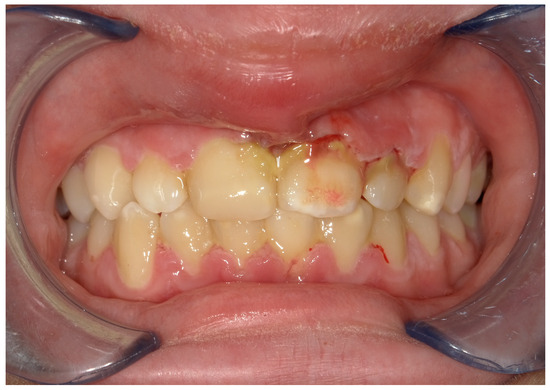

4.2. Case 2